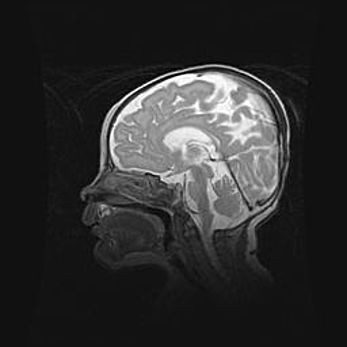

Аномалия Денди-Уокера. Признаки гипоплазии мозолистого тела.

Возраст: 5 месяцев 3 дня

Вес: 5550 г

Пол: мужской

Окружность головы: 39 см

Срок гестации: 40 недель

Аномалия Денди-Уокера – это порок развития головного мозга, для которого характерна триада симптомов: гипотрофия или аплазия червя мозжечка и/или полушарий мозжечка, расширение четвёртого желудочка с формированием ликворной кисты задней черепной ямки, гипертензионная гидроцефалия различной степени.

Гипоплазия мозолистого тела относится к дефектам внутриутробного этапа развития мозговой ткани, возникающим в процессе закладки структур головного мозга, что происходит на начальных этапах развития эмбриона.